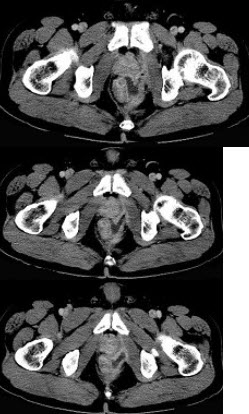

男,28岁,高热,肛门坠胀,频有便意,直肠指诊时触及直肠粘膜下饱满,柔软,压痛的肿块,CT检查如图,诊断为( )

A:直肠癌

B:直肠炎性息肉

C:直肠粘膜下脓肿

D:直肠绒毛状腺瘤

E:直肠粘膜下瘘